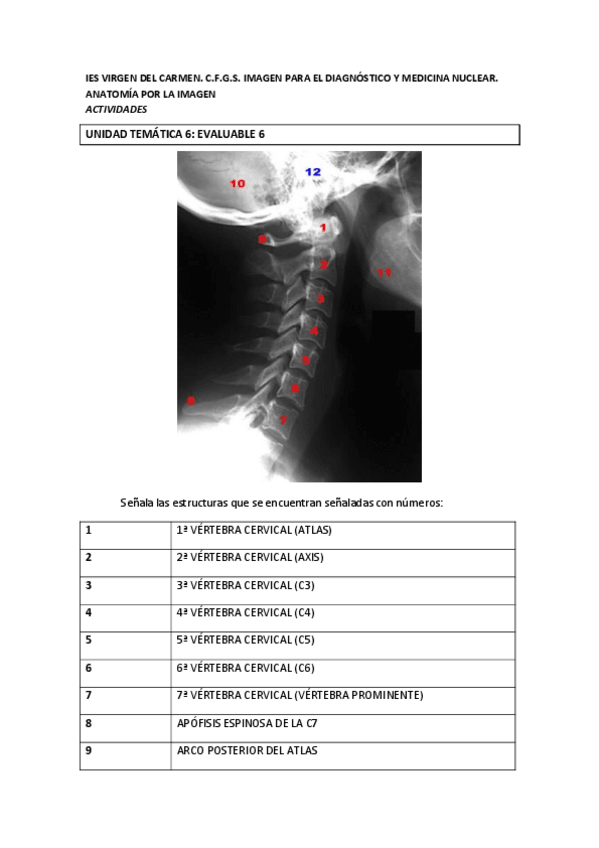

EVALUABLE-6-vertebras-RESUELTA66d67108d482c4c5a1977c4a315ef0aa.pdf